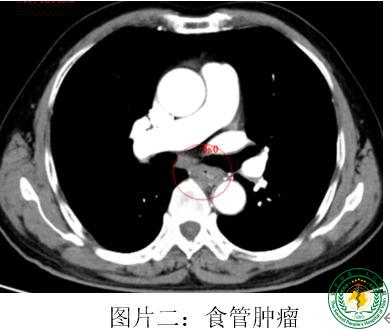

宜宾首例!我院成功开展胸部单操作孔胸腔镜食管癌联合肺癌根治手术

宜宾首例!我院成功开展胸部单操作孔胸腔镜食管癌联合肺癌根治手术57497